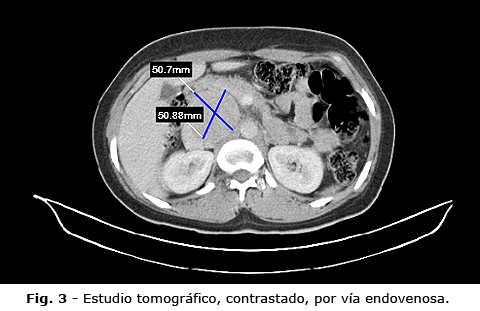

Los exámenes de laboratorio clínico, estaban dentro de límites normales. Se realizó un ultrasonido en el cual se informó (Fig. 1): hígado y vías biliares de aspecto normal, vesícula con litiasis en la proyección del cuerpo, de 7 mm de diámetro; bazo, páncreas y riñones normales, no adenopatías profundas visibles. Se observa imagen nodular, hipoecoica de ecoestructura homogénea, contornos regulares, de 74 x 58 mm de diámetro en proyección del lóbulo caudado del hígado, cabeza de páncreas y marco duodenal, retroperitoneal, separado de las estructuras vecinas. Resto del barrido abdominal negativo. Vejiga vacía.